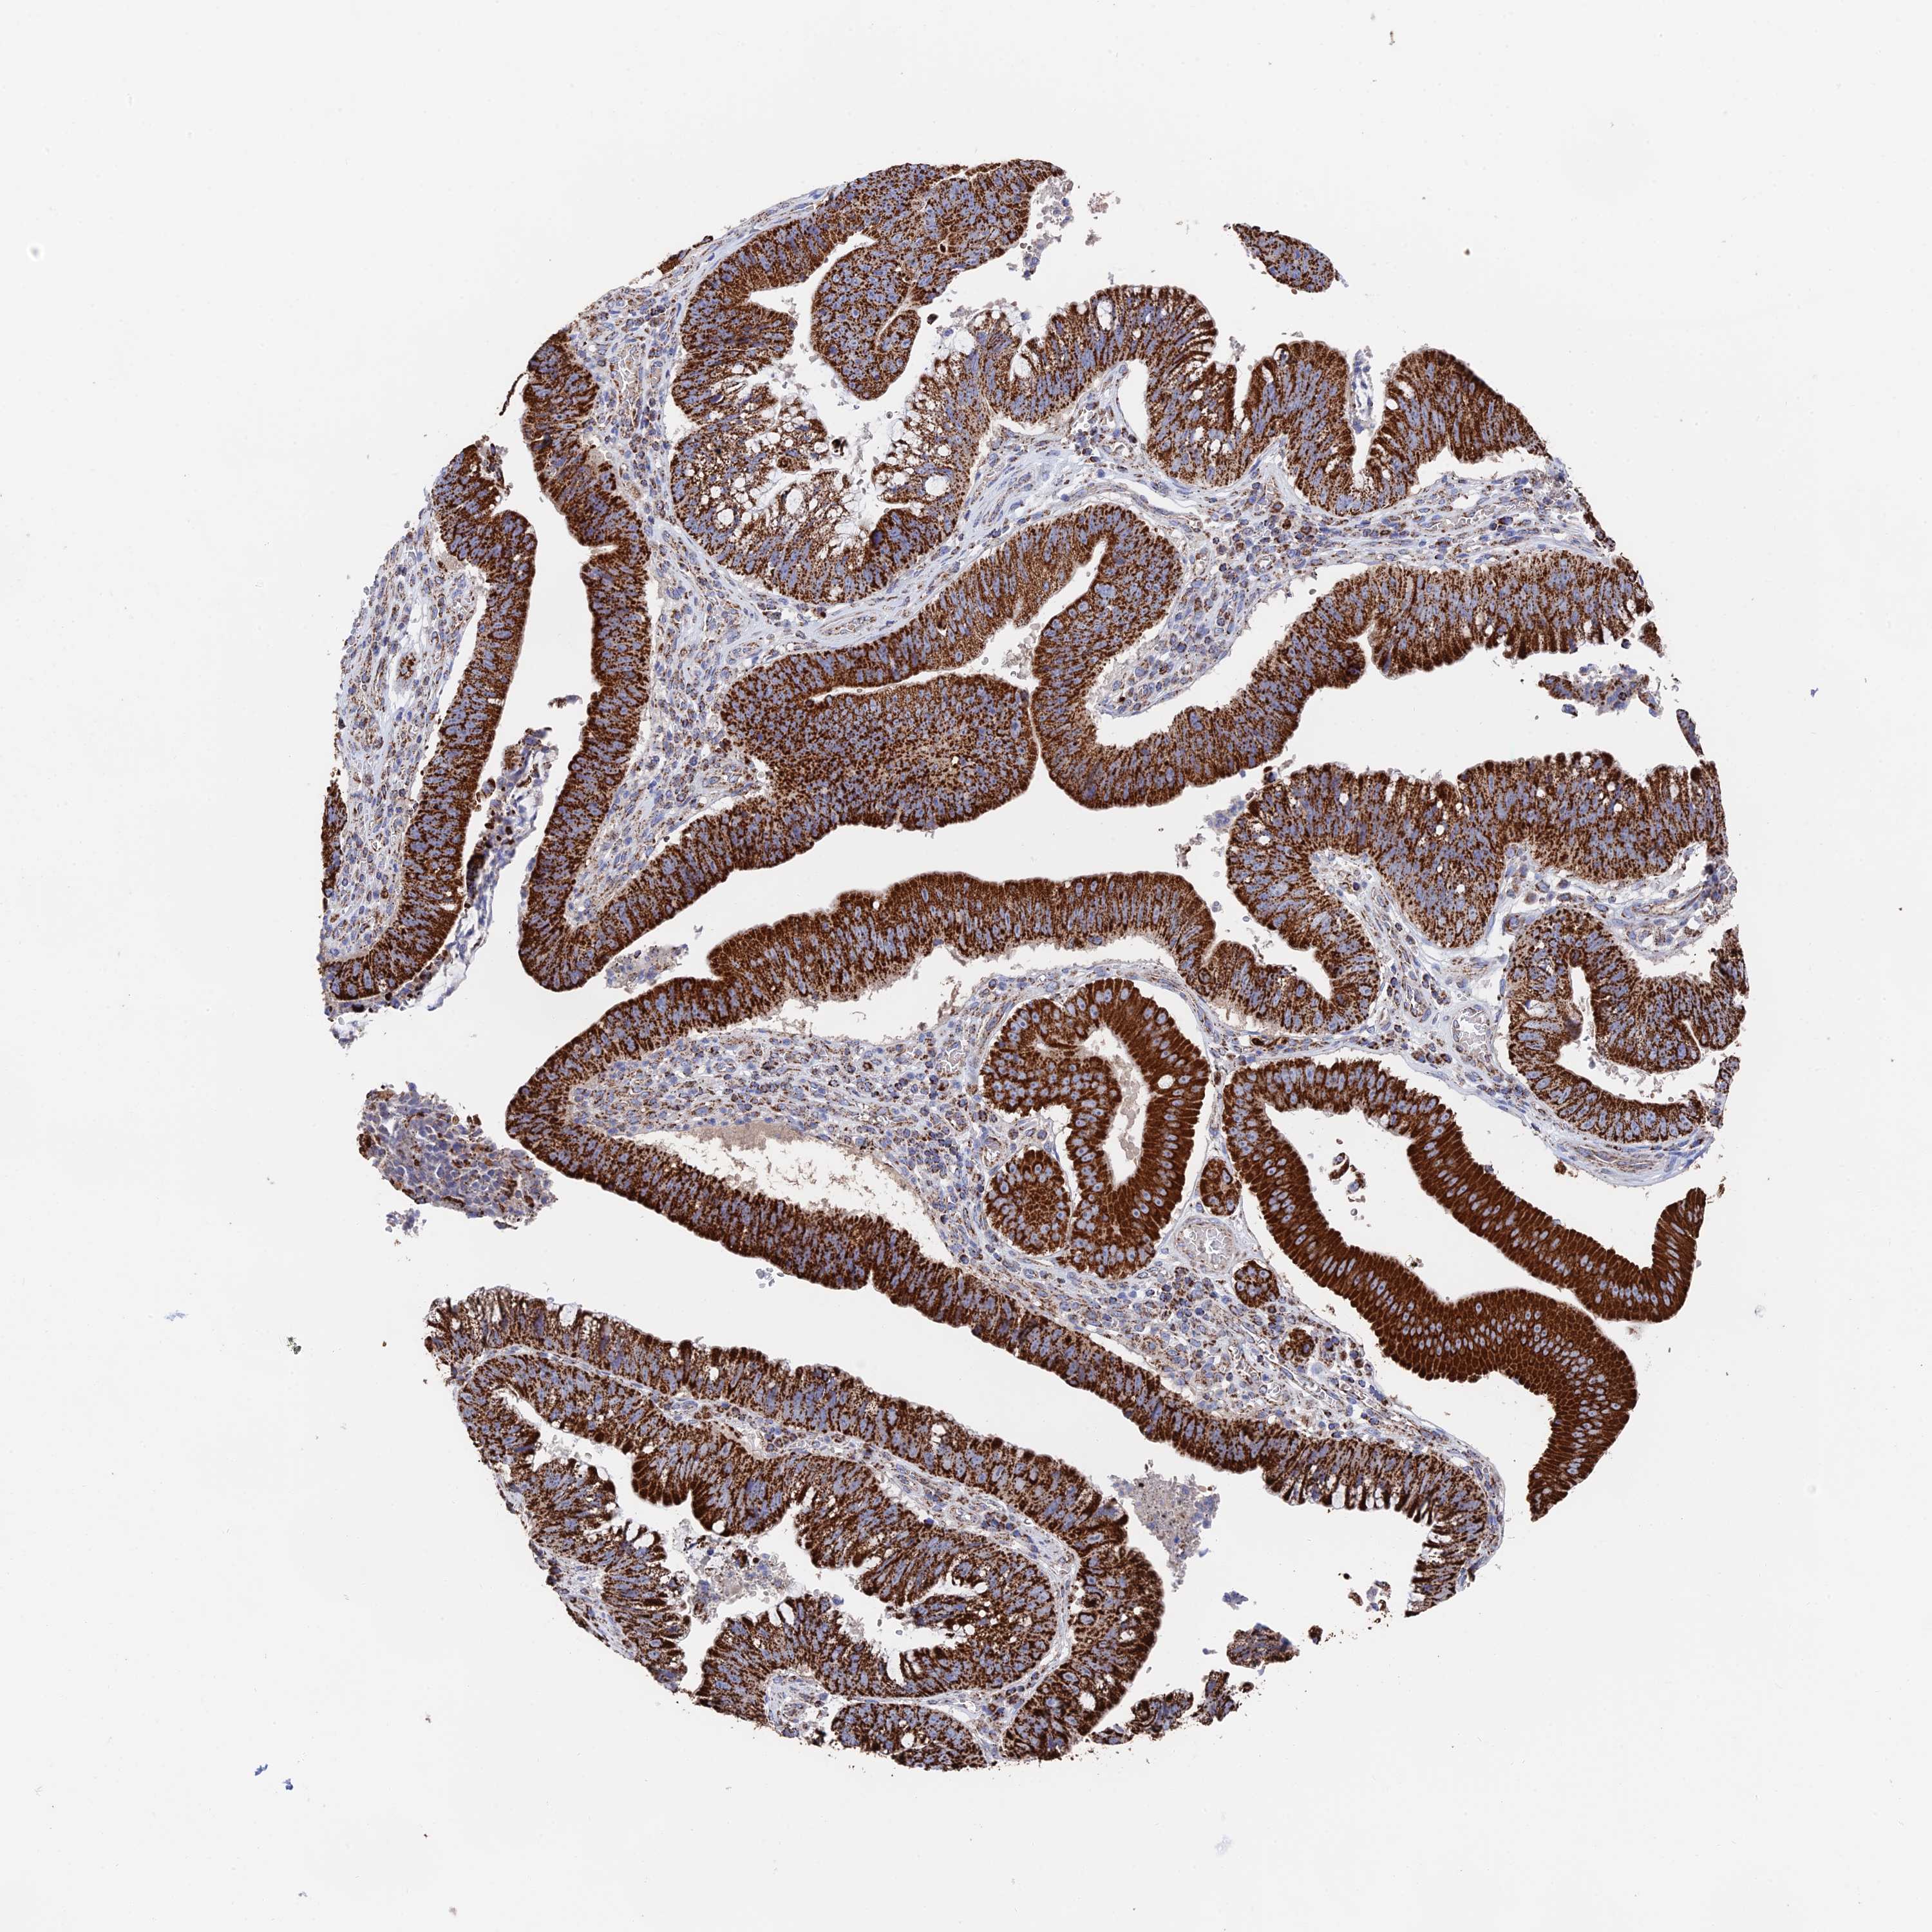

STOMACH CANCER - Protein expressioni

A mouse-over function shows sample information and annotation data. Click on an image to view it in a full screen mode. Samples can be filtered based on level of antibody staining by selecting one or several of the following categories: high, medium, low and not detected. The assay and annotation is described here.

Note that samples used for immunohistochemistry by the Human Protein Atlas do not correspond to samples in the TCGA dataset.

Antibody stainingi

Antibody staining in the annotated cell types in the current human tissue is reported as not detected, low, medium, or high, based on conventional immunohistochemistry profiling in selected tissues. This score is based on the combination of the staining intensity and fraction of stained cells.

Each image is clickable and will lead to virtual microscopy that enables deeper exploration of all samples and also displays staining intensity scores, fraction scores and subcellular localization as well as patient and tissue information for each sample.

Antibody HPA039406

Staining

High

Medium

Low

Not detected

Intensity

Strong

Moderate

Weak

Negative

Quantity

>75%

75%-25%

<25%

None

Location

Nuclear

Cytoplasmic/membranous

Cytoplasmic/membranous,nuclear

Adenocarcinoma, NOS